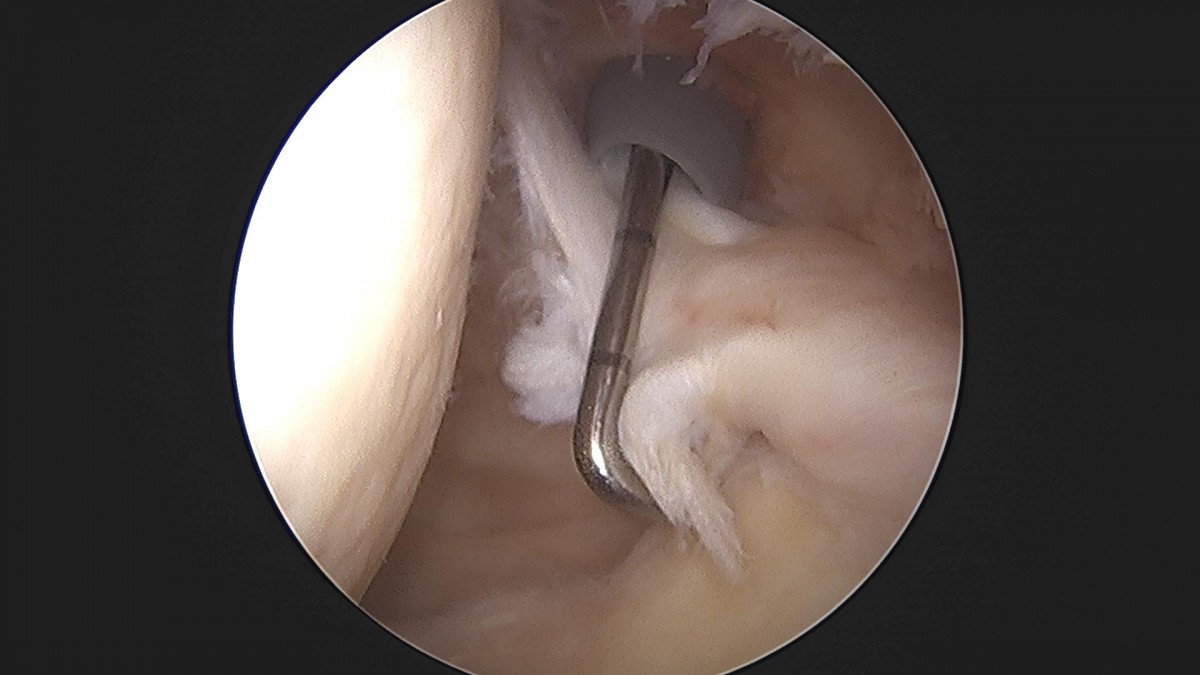

이재상원장님 어깨 회전근개봉합술(3933)김명O 환자

작성자 최고관리자 댓글 0건 조회 1,313회 작성일 22-04-12 18:13